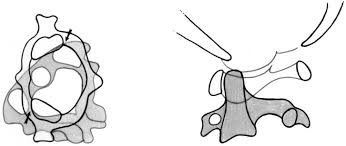

CVJ Anomaly

Our neurosurgeon specializes in the treatment of craniovertebral junction (CVJ) anomalies, providing expert care and interventions to optimize neurological health and ensure proper alignment of the skull and spine.